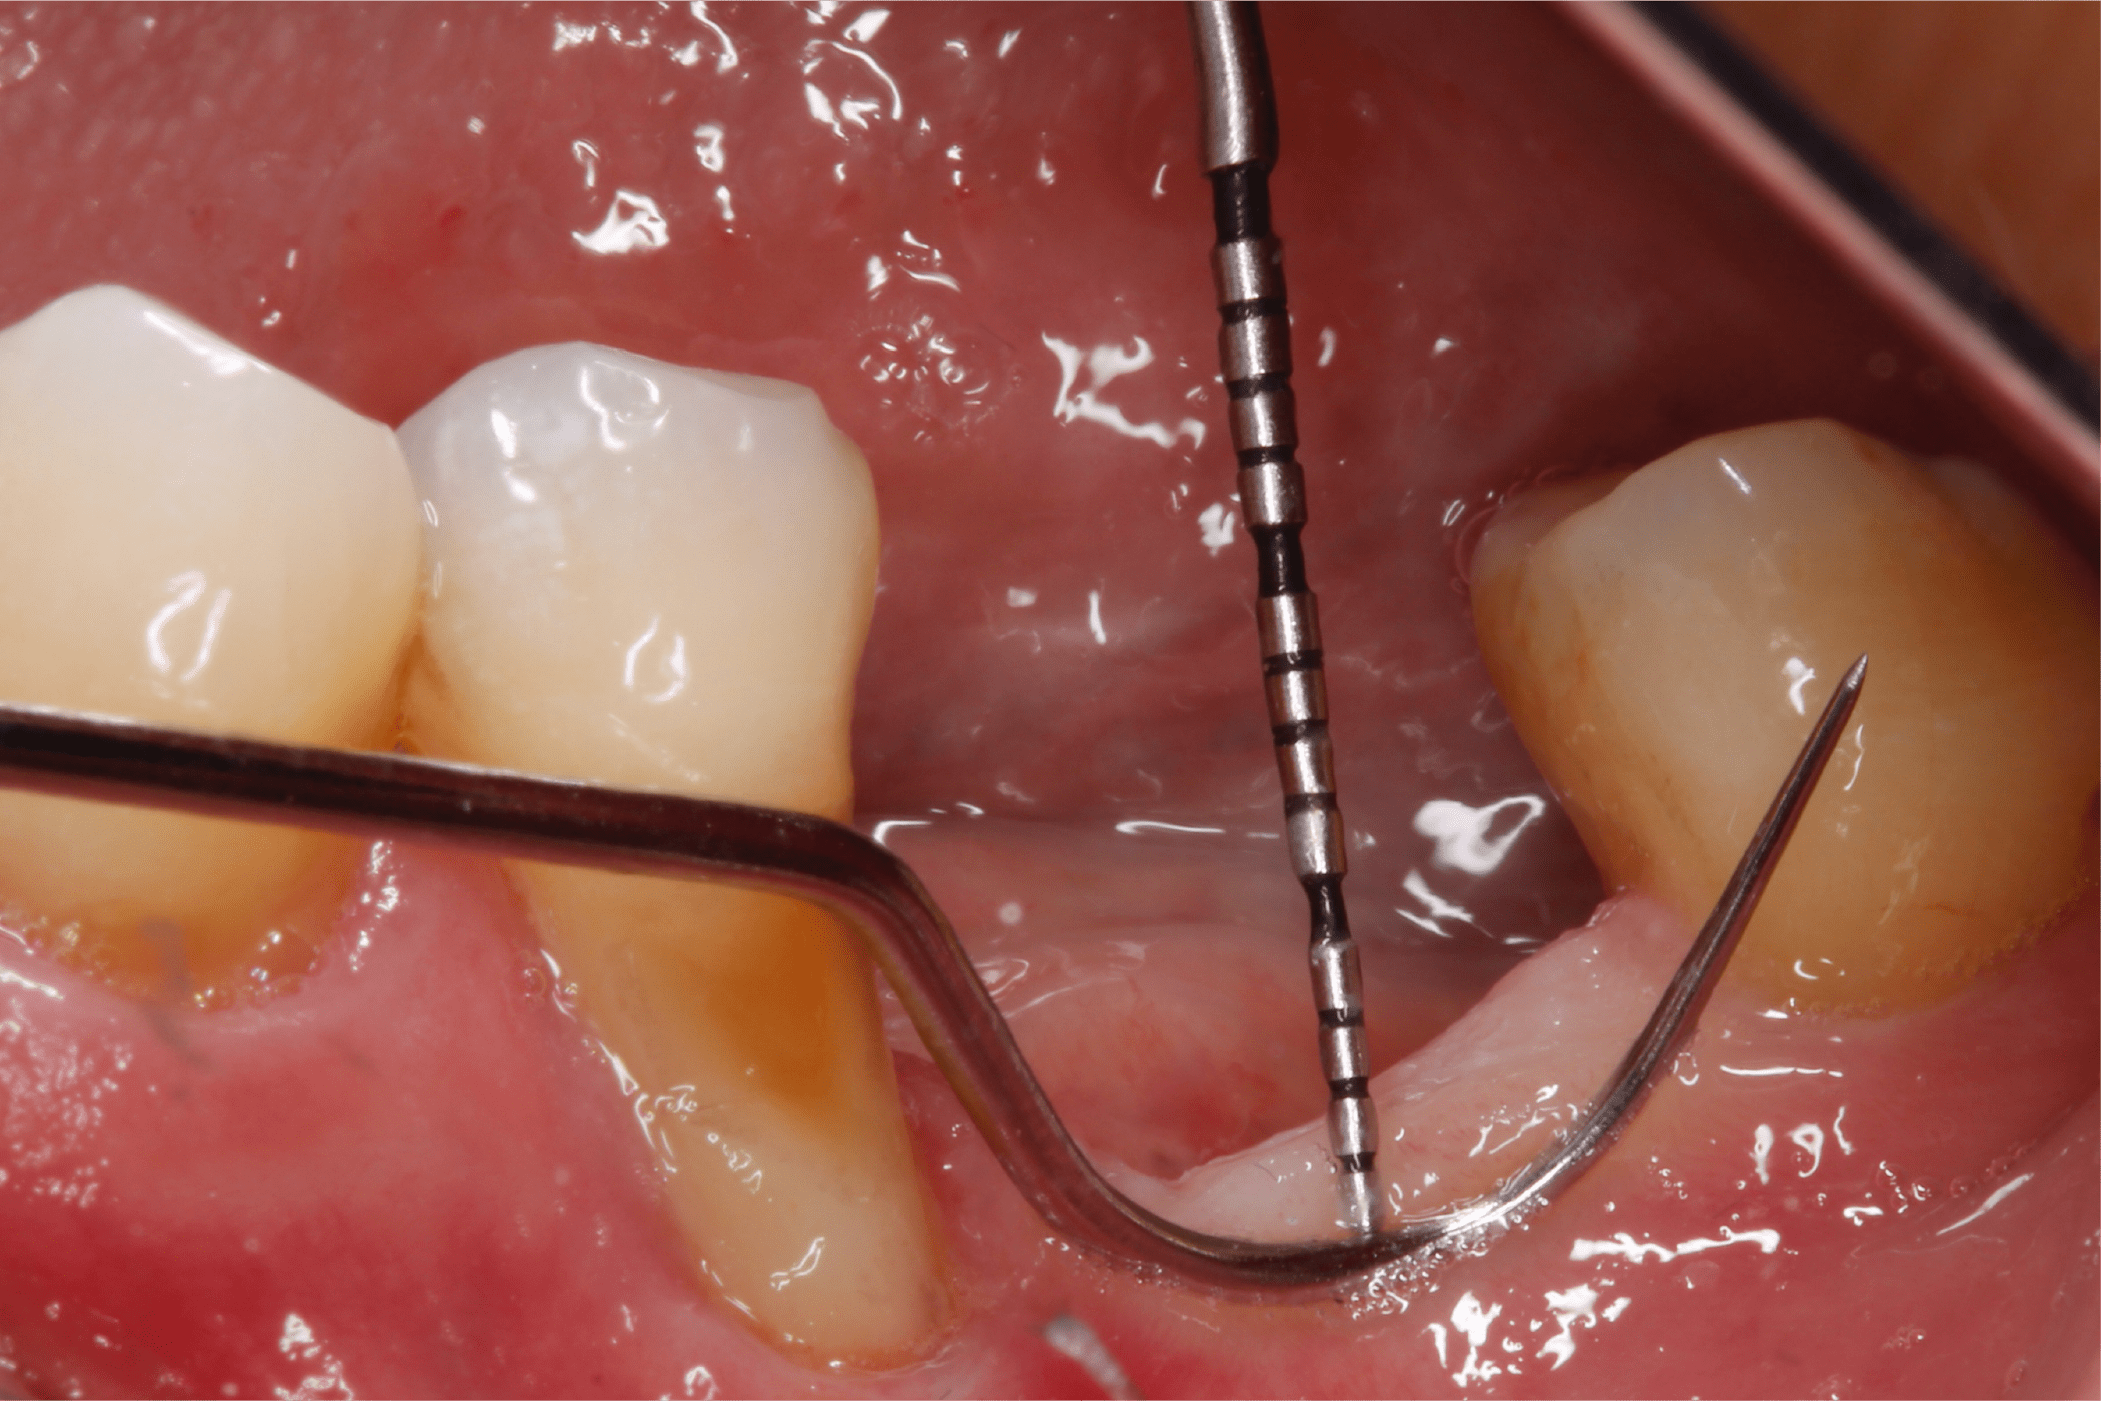

Tras un enjuague antiséptico, se anestesia la zona a tratar y se procede a preparar el lecho receptor por medio de incisiones de espesor parcial dejando periostio expuesto, esto con la intención de darle aporte vascular al injerto. (Fig. 6 y 7).

Posteriormente se realizan mediciones y se toma el IGL del paladar (Fig. 8).

Fig. 6

Fig. 7

Fig. 8